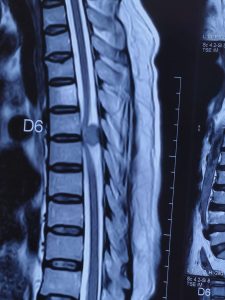

मधेश प्रदेशमा पहिलाे पटक जानकी एकेडेमीक हस्पिटलमा डा.प्रधुम्न कुमार यादव र वहाँ काे टिम ले Neuro Surgical of Spinal (D6 Spine Tumer excision ) केश सफलतापुर्ण अप्रेसन गरिएकाे छ । अहिले सम्म यस्तो जटिल (D6 Spine Tumer) को अप्रेसन धनुषा जिल्ला को जनकपुर र विरगंजमा मा पनि भएकाे छैन ।